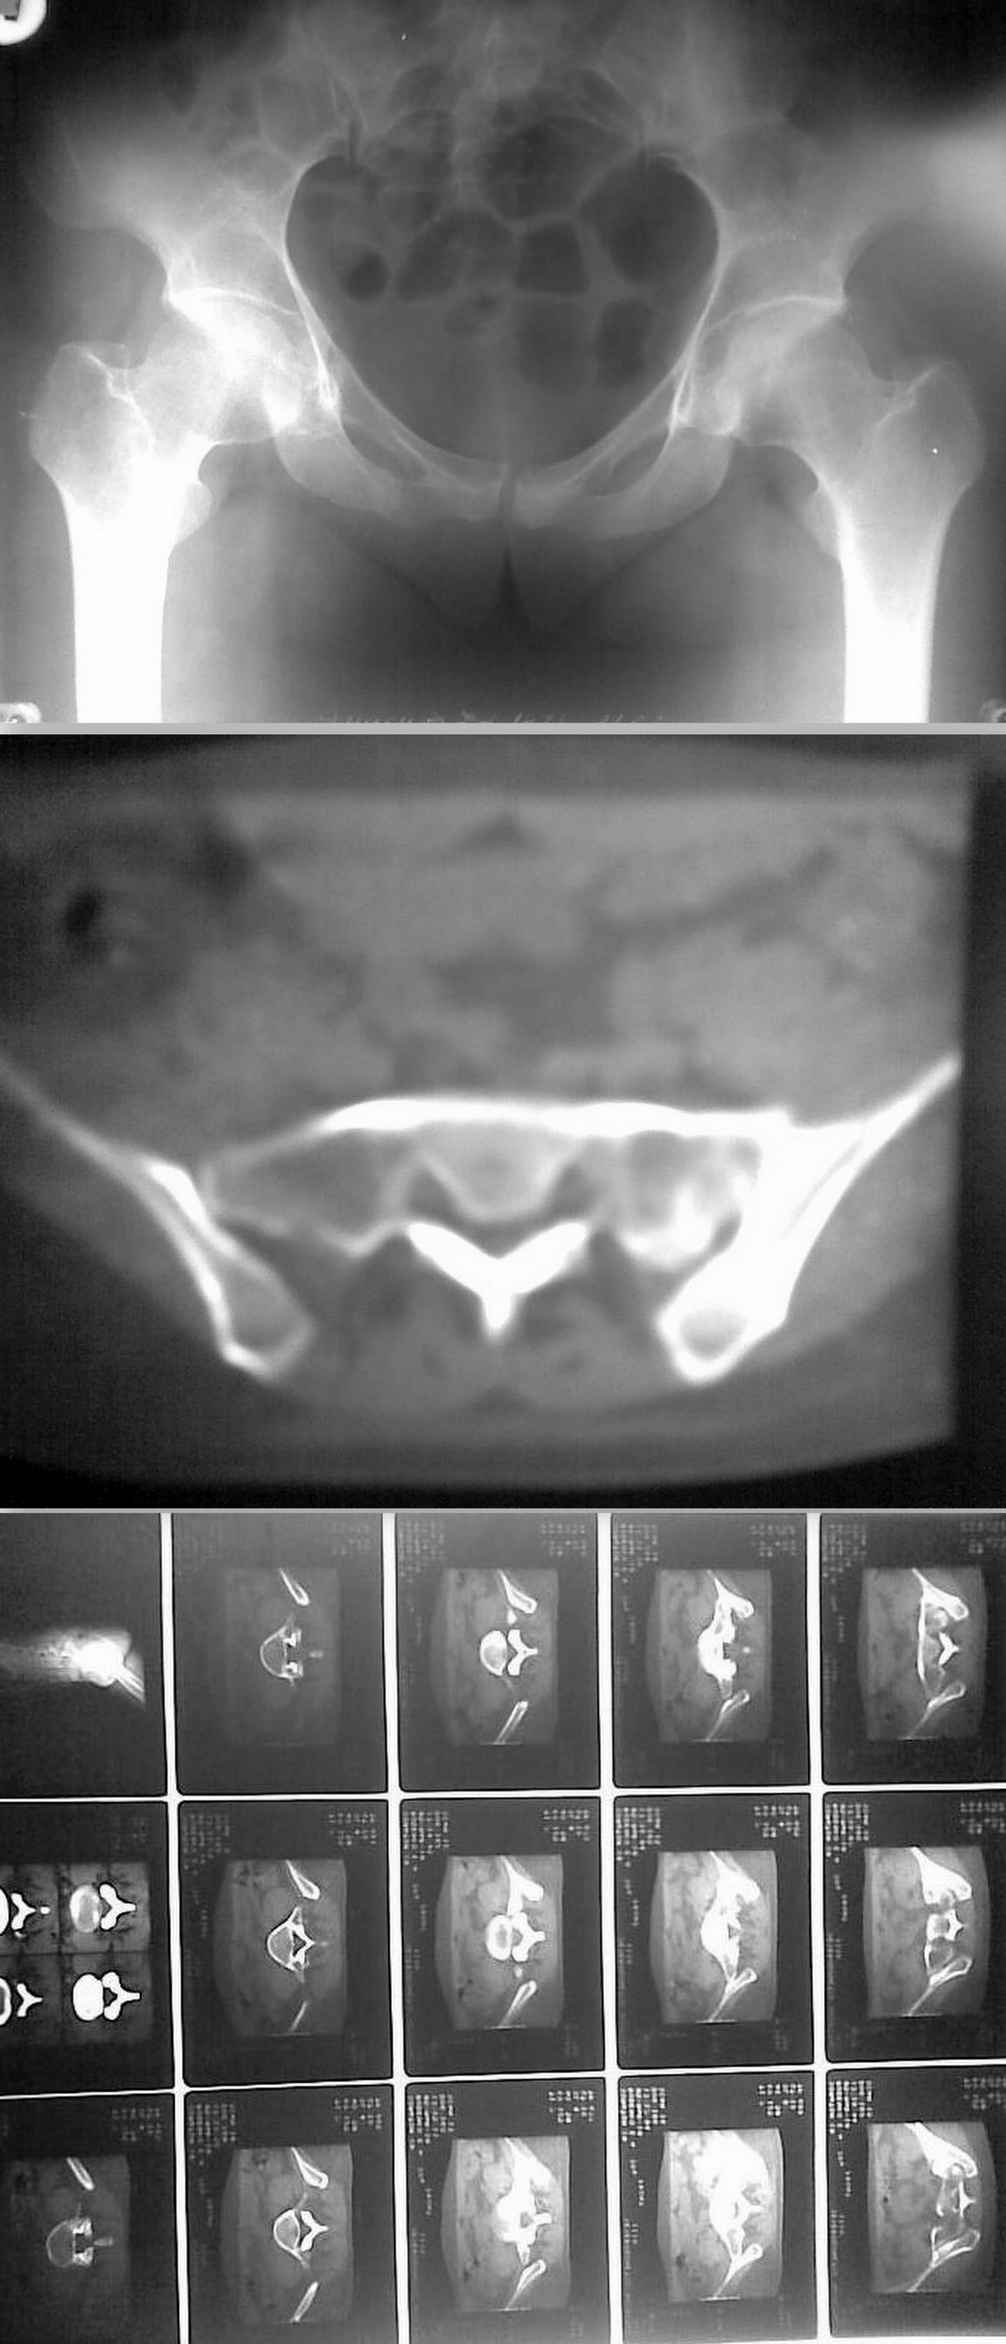

Добрый вечер, уважаемые коллеги. Представляю на обсуждение случай "несвежего" перелома крестца. Больная 32 лет поступила в отделение 02.03.10. Травма 26.12.09 ДТП в качестве пассажира (сидела сзади, машина перевернулась). Находилась на амбулаторном(?)лечении с диагнозом "перелом седалищной кости справа". Через 2 месяца после травмы больная вертикализирована, но отмечались интенсивные боли в поясничном отделе с иррадиацией по задней поверхности бедра. Больная направлена в стационар. Выполнена КТ. Картина в приложении. Как лучше поступить? Оставить "как есть" и продолжить консервативное лечение? Оперировать? Другие варианты? С уважением Д.Б.

Уважаемый Дмитрий, по R-графии складывается впечатление о озлокачествленной ОБК (выражена деструкция крестца). При ректальном пальцевом исследовании данная опухоль должна четко пропальпироваться. Очевидно, лечение симптоматическое совместно с онкологом.

Пример из практики: возраст женщины аналогичен, обращалась в травмпункт с ушибом крестца, на первичной ренгенограмме деструкция крестца не выявлена, болевой синдром прогрессировал, на последующих ренгенограммах через 2 месяца и через 6 месяцев прогрессирование деструкции крестца. R-граммы прилагаю.

ректально вроде чисто, нет ничего. Да и на КТ признаков деструкции не заметно... Спасибо за онконастороженнность, будем думать.

Доброго времени суток! Уважаемый коллега! К сожалению качество рисунка желаеть лучшего, трудно было рассмотреть данные КТ. На КТ захватили поясничный отдел позвоночника? С уважением Ерсин Жунусов.

отправляю КТ в лучшем качестве

Приветствую! Необходимо исключить изменения в поясничном отделе позвоночника. Иногда, причиной такого характера болей является перелом поперечного отростка L5. И по поводу крестца - консервативная терапия. Нагрузка не ранее 10-12 нед.